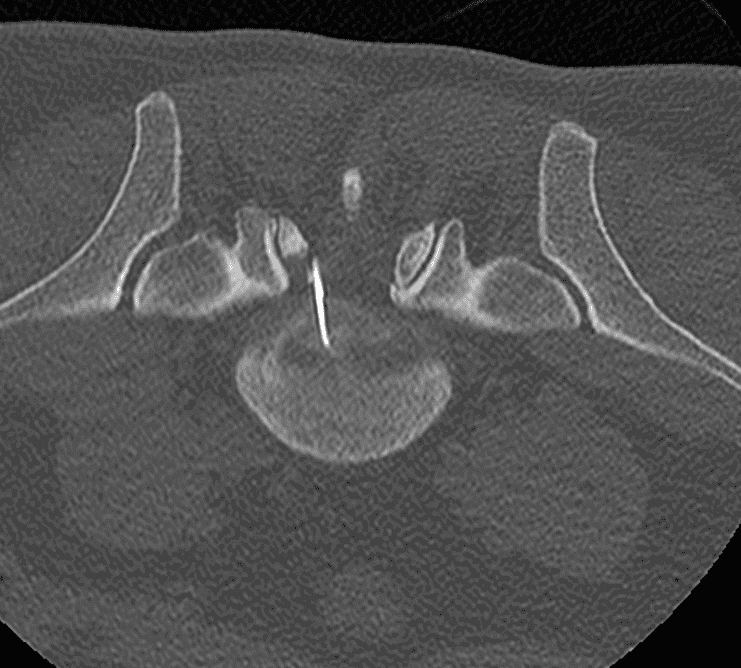

Scanner

Une imagerie (scanner ou IRM) est réalisée en amont pour établir le diagnostic, évaluer l’anatomie discale et planifier la trajectoire d’insertion.

Le guidage en temps réel par fluoroscopie ou scanner assure une précision optimale, minimisant ainsi le risque de lésion des structures adjacentes.

Une fois l’aiguille en place, des instruments spécialisés (curettes ou dispositifs aspiratifs) sont utilisés pour retirer une portion du noyau pulpeux.

Cette résection permet de diminuer la pression interne, facilitant le repositionnement du disque et la réduction de la hernie.

Contrôle final

Un contrôle imagerie est effectué en fin d’intervention pour vérifier la qualité de la décompression et la bonne répartition des espaces discaux, garantissant ainsi l’efficacité du geste.